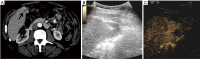

Background: To assess the technical success of contrast enhanced ultrasound (CEUS) guided biopsies of liver lesions poorly visualized on B-mode ultrasound.

Methods: Patients were selected during the procedure based on the real-time clinical scenario of unsatisfactory B-mode ultrasound lesion visualization and all patients would have otherwise undergone CT guided liver lesion biopsy. A total of 26 patients underwent CEUS guided biopsy and were included in this retrospective analysis. The review of the patients' files included demographic information, lesion characteristics on imaging, procedural details and pathology outcome. Technical success was defined as concordance between the radiological findings, pathology report and clinical follow-up-demonstrating lack of need for re-biopsy or re-biopsy with identical pathological results. Patients with less than 2 months follow-up were excluded from the study.

Results: CEUS guided liver biopsy was successful in 23 out of 26 patients (88.5%). The average procedure time was 30.7±12.3 minutes and the average lesion size was 2.2±1.7 cm. The majority of lesions (80.8%) were hypoenhancing on the delayed phase of CEUS. The mean number of samples taken from each lesion per procedure was 3.2 (±1.7).

Conclusions: CEUS guidance biopsies of focal liver lesions (FLL) that were difficult to visualize on B-mode ultrasound demonstrated high success rate and may be an evolving image guidance modality in selected patients to avoid CT guided procedures.